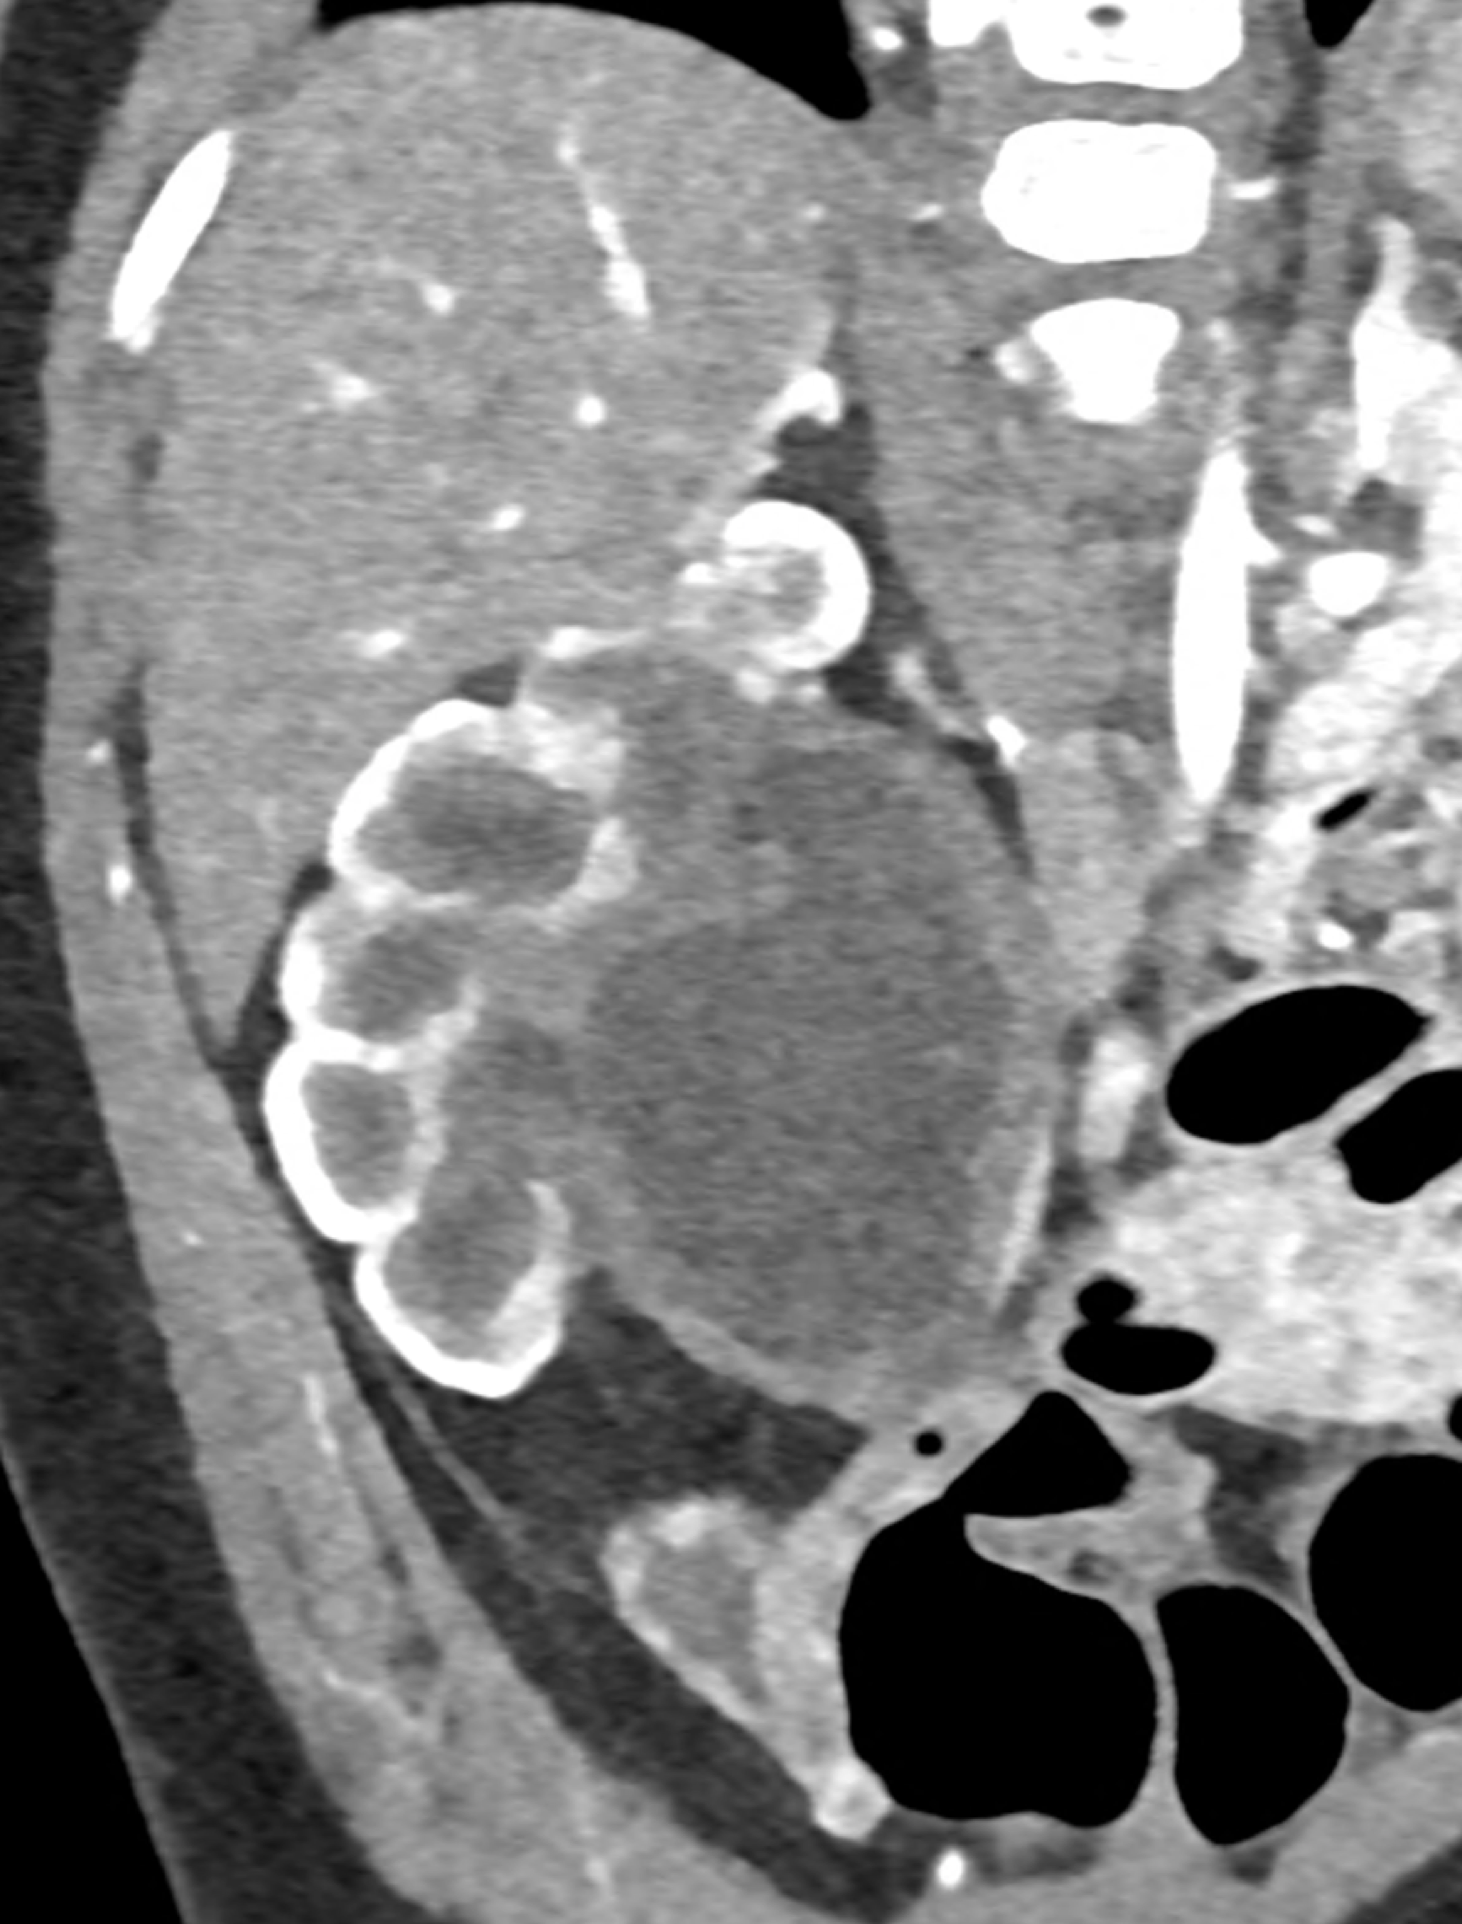

in patient chest pain, negative ECG but with elevated D-dimers was performed CTA of the chest to exclude highly suspected pulmonary embolism. No pulmonary embolism was see, but the pathology of the aortic arch and descending thoracic atorta. The images were consistent with aortic intramural hematoma type B according to the Stanford classification with incipient transformation in dissection – behind the subclavian artery, it is clear that the contrast agent is flowing into the intramural hematoma. Differentiation from wall thrombosis is facilitated by the presence of calcification in the detached intima, which is most clearly visible on virtual non-contrast imaging. The intramural hematoma itself exhibits different properties in terms of X-ray absorption. Coagulated blood is visible at the apex of the aortic arch, where it closely adjoins the area that is perfused and filled with contrast medium. There are other smaller areas filled with contrast medium at the sites of the intercostal arteries. These areas are secondary sites where the original intramural hematoma is channeled during its transformation into a classic aortic dissection.

Virtual non-contrast images help to distinguish between the intima and thus in the differential diagnosis of intramural hematoma versus wall thrombosis. Signs of fresh coagulated blood in IMH indicate bleeding into the aortic wall from the vasa vasorum. In contrast, monoenergetic images with lower energies of 40-55 keV highlight areas of intramural hematoma with active blood flow.

comparison of the the images 60, keV monoenergetic, virtual non-contrast (VNC), and iodine map images. The repercussion starts in the proximal tear of the intimate (the first three images), calcification in the intimate (next three images), tera at the level of the arising intercostal artery (last three images)

comparison of the perpendicular planes to sagittal aortic MPR in 40, 60, 140 and 190 keV monoenergetic images